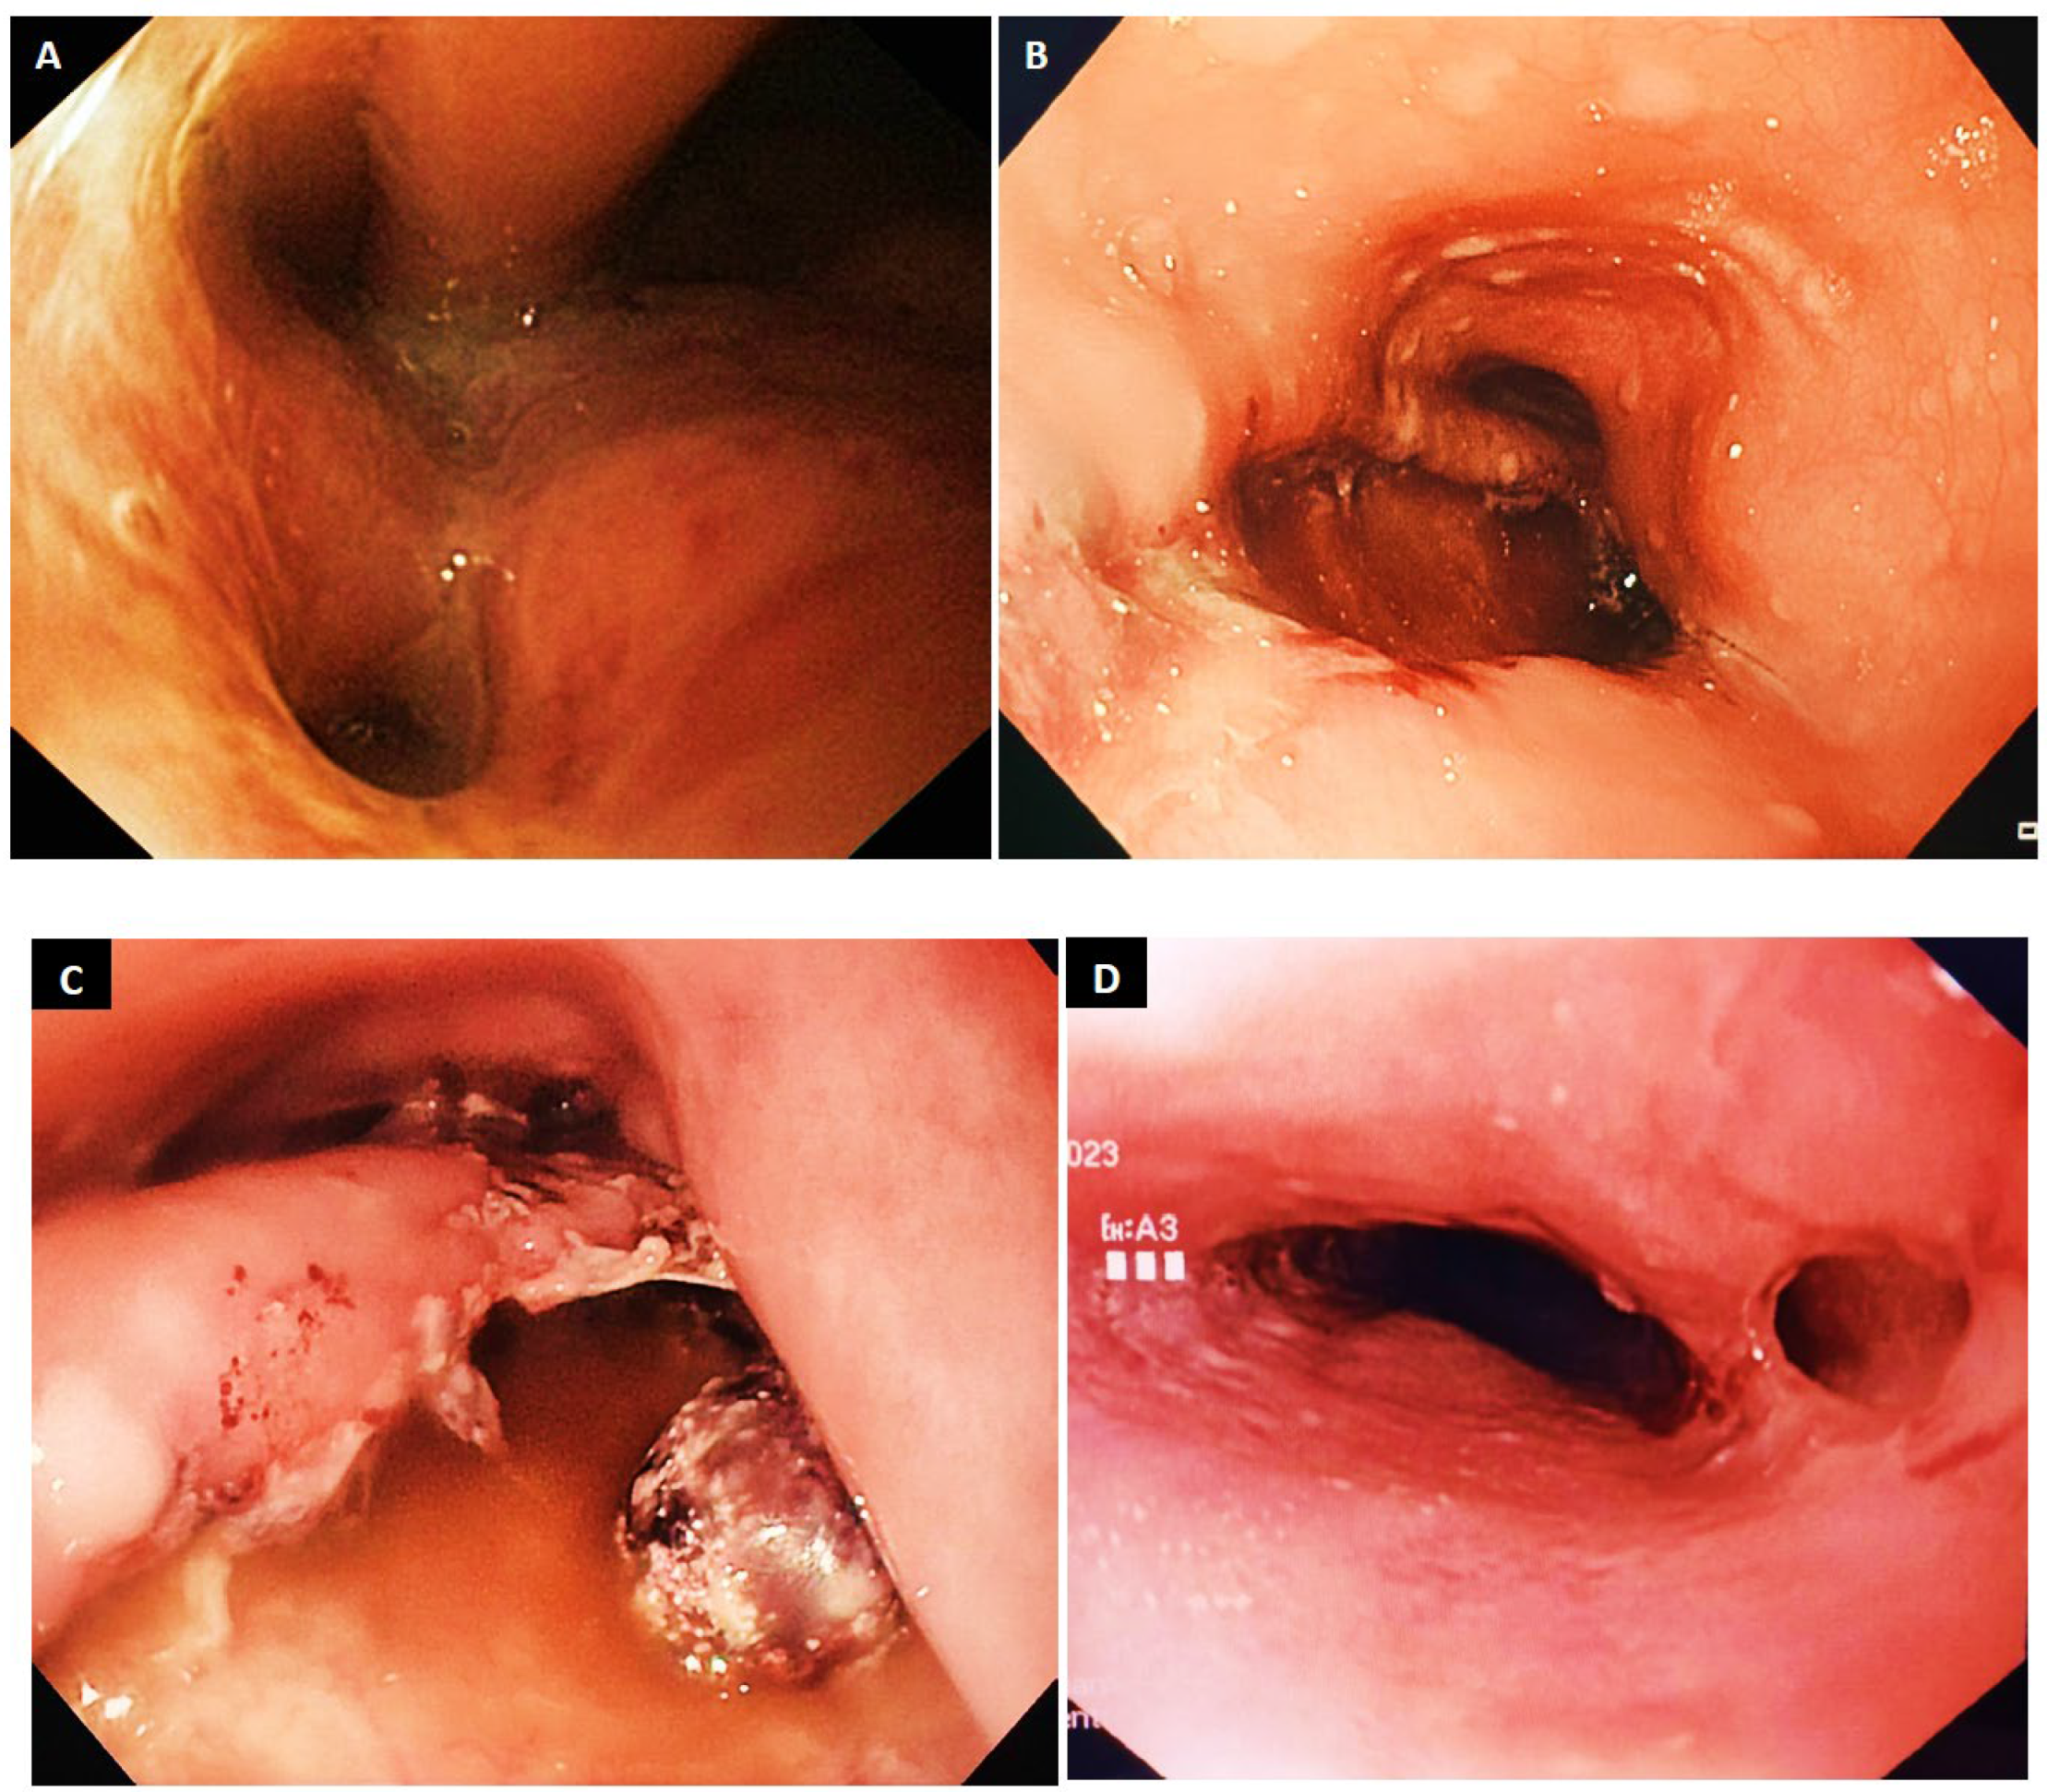

9.3. Clip Placement

9.4. Stent Placement

- Dickinson, K.J.; Buttar, N.; Song, L.M.W.K.; Gostout, C.J.; Cassivi, S.D.; Allen, M.S.; Nichols, F.C.; Shen, K.R.; Wigle, D.A.; Blackmon, S.H. Utility of endoscopic therapy in the management of Boerhaave syndrome. Endosc. Int. Open 2016, 4, E1146–E1150. [Google Scholar] [CrossRef]

- Dickinson, K.J.; Blackmon, S.H. Endoscopic Techniques for the Management of Esophageal Perforation. Oper. Tech. Thorac. Cardiovasc. Surg. 2015, 20, 251–278. [Google Scholar] [CrossRef]

- Gurwara, S.; Clayton, S. Esophageal perforations: An endoscopic approach to management. Curr. Gastroenterol. Rep. 2019, 21, 57. [Google Scholar] [CrossRef]

- Cortázar, E.V.; Aguirre, P.A. Endoscopic management of Boerhaave’s syndrome. Rev. Esp. De Enfermedades Dig. 2019, 111, 493. [Google Scholar] [CrossRef]

- JEstorninho, J.; Pimentel, R.; Gravito-Soares, M.; Gravito-Soares, E.; Amaro, P.; Figueiredo, P. Successful Endoscopic Closure of Esophageal Perforation in Boerhaave Syndrome Using the Over-the-Scope Clip. GE-Port. J. Gastroenterol. 2022, 30, 444–450. [Google Scholar] [CrossRef] [PubMed]

- Musala, C.; Eisendrath, P.; Brasseur, A.; Vincent, J.-L.; Cappeliez, S.; Moine, O.; Devière, J.; Lemmers, A. Successful treatment of Boerhaave syndrome with an over-the-scope clip. Endoscopy 2015, 47, E24–E25. [Google Scholar] [CrossRef]

- González-Haba, M.; Ferguson, M.K.; Gelrud, A. Spontaneous esophageal perforation Boerhaave syndrome successfully treated with an over-the-scope clip and fully covered metal stent. Gastrointest. Endosc. 2015, 83, 650. [Google Scholar] [CrossRef] [PubMed]